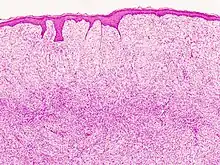

| Histopathological image of dermatofibrosarcoma protuberans. Local recurrence long after the first excision. H&E stain | |

- Subcutaneous tissue infiltration (i.e. "honeycomb" growth pattern)

- Monotonous, plexiform structure of tumour

- DFSP formed both by fibroblastic and histiocytic elements

- Hemosiderin deposits beneath the tumour

- Immunostain positive for CD34